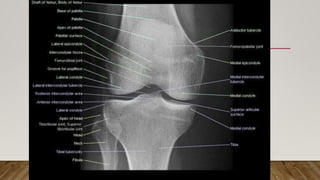

This document discusses radiology and the use of x-rays. It begins with an introduction to radiology and x-rays, noting their importance as the "father of medical investigations." It then discusses anatomy as seen on radiographs and whether x-rays are enough. The document goes on to compare gross views to radiological views, noting what each can and cannot show. It highlights important figures in the development of radiology, from x-rays to CT, MRI, and ultrasound. Specific anatomical structures visible on upper and lower limb x-rays are listed. The document concludes by discussing how pathologies appear on x-rays and the importance of clinical history and knowledge when interpreting radiological images.